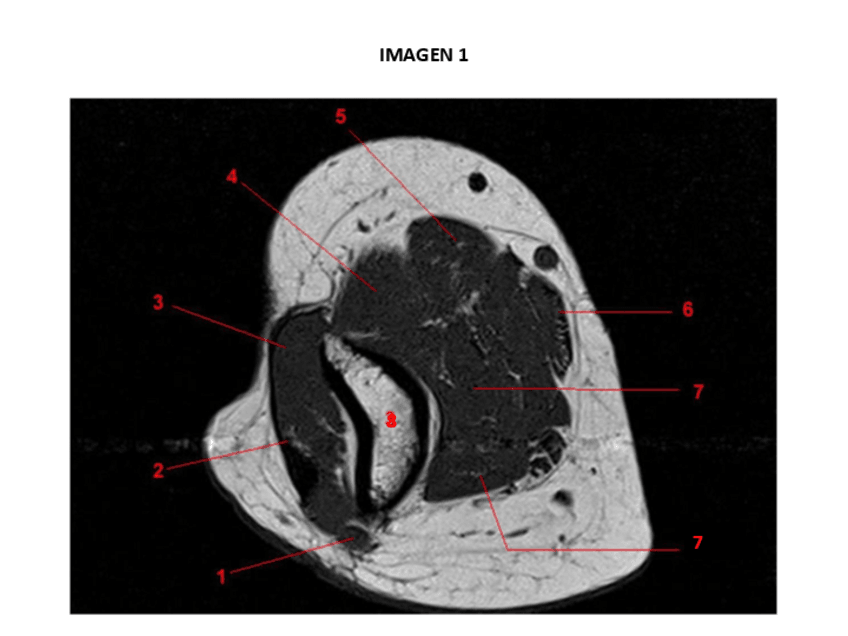

Imágenes de prácticas con respuestas

He publicado nuevos practicas de 3º Anatomía Humana a Través de la Imagen: Imágenes de prácticas con respuestas